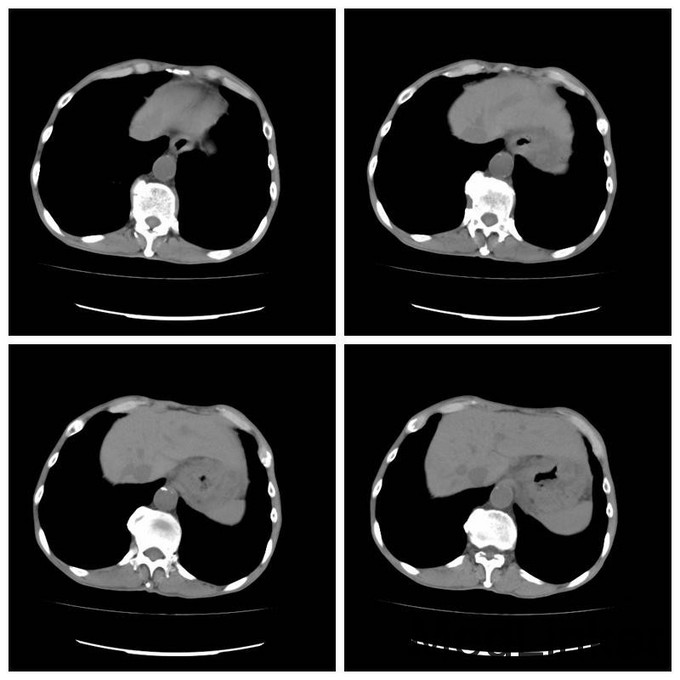

患者中年男性,50岁 主诉:腹部反复不适2年,腹痛1月 现病史:患者约于2年前反复出现腹部不适,无明显腹痛,纳差,不伴恶心呕吐,近2月来无明显诱因体重减轻5kg,曾经解黑便数次,具体时间和量不详,无明显恶心呕吐。近1月来出现腹部疼痛,中上腹部疼痛为主,疼痛多呈隐隐作痛,可耐受,站立时头晕。 既往史:既往体健

查体:无明显阳性体征 辅助检查:Hb80g/L CT及胃镜均提示胃癌

诊断:胃癌 治疗:腹腔镜下全胃切除术